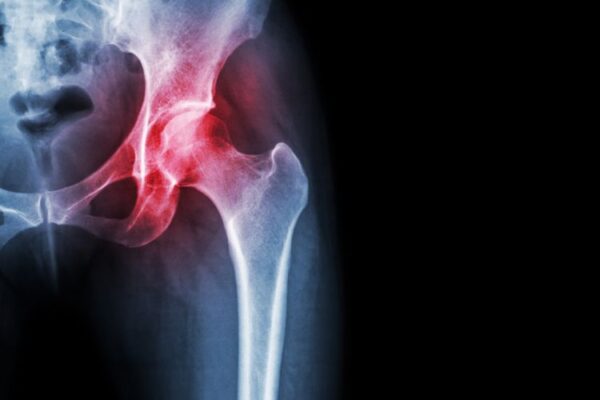

Οι μεγαλύτερες αρθρώσεις του ανθρώπινου σώματος είναι τα γόνατα και τα ισχία (γοφοί). Υποστηρίζουν όλο το σωματικό βάρος και λειτουργούν σε στενό συντονισμό, έτσι ώστε να μπορούμε να βαδίζουμε, να τρέχουμε, να αθλούμαστε και να σηκώνουμε βάρος.

Με την πάροδο του χρόνου, πολλοί αρχίζουν να αισθάνονται πόνο λόγω της οστεοαρθρίτιδας, μιας διαδικασίας φθοράς των αρθρώσεων από την υπέρχρηση και καταπόνησή τους. Με πόνο στο γόνατο ή στο ισχίο οι ασθενείς ξεκινούν  φυσικοθεραπεία, να παίρνουν φάρμακα για ανακούφιση, να κάνουν ήπιες παρεμβάσεις, αρθροσκόπηση και ενέσεις για ανακούφιση από τον πόνο.

Αλλά για μερικούς, τα προβλήματα στο γόνατο και στο ισχίο γίνονται τόσο δύσκολα που η αντικατάστασή τους προσφέρει την καλύτερη ευκαιρία για επιστροφή στην κανονικότητα χωρίς πόνο. Η αρθροπλαστική γόνατος είναι μια αποδεδειγμένα αποτελεσματική χειρουργική επέμβαση για την ανακούφιση του πόνου και την αποκατάσταση της λειτουργίας της άρθρωσης. Ωστόσο, η ποιότητα και η πληρότητα των αποτελεσμάτων στην οποία επιτυγχάνονται αυτοί οι στόχοι είναι μεταβλητοί.

Το ισχίο είναι πιο απλή άρθρωση ενώ το γόνατο πρέπει να εξισορροπήσει  φορτία πιο μακριά από το κέντρο βάρους αλλά και να κάνει πιο πολύπλοκες κινήσεις. Μια ολική αντικατάσταση γόνατος, αφαιρεί περισσότερο ιστό αλλά και οστό. Ο μετεγχειρητικός πόνος είναι περισσότερος στην αρθροπλαστική του γόνατος αφού τα μαλακά μόρια επηρεάζονται από τη χειρουργική επέμβαση περισσότερο από ό,τι τα μαλακά μόρια γύρω από το ισχίο.